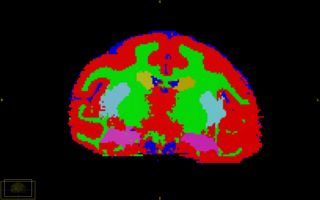

Segmentation of major tissue classes in for vervet subject